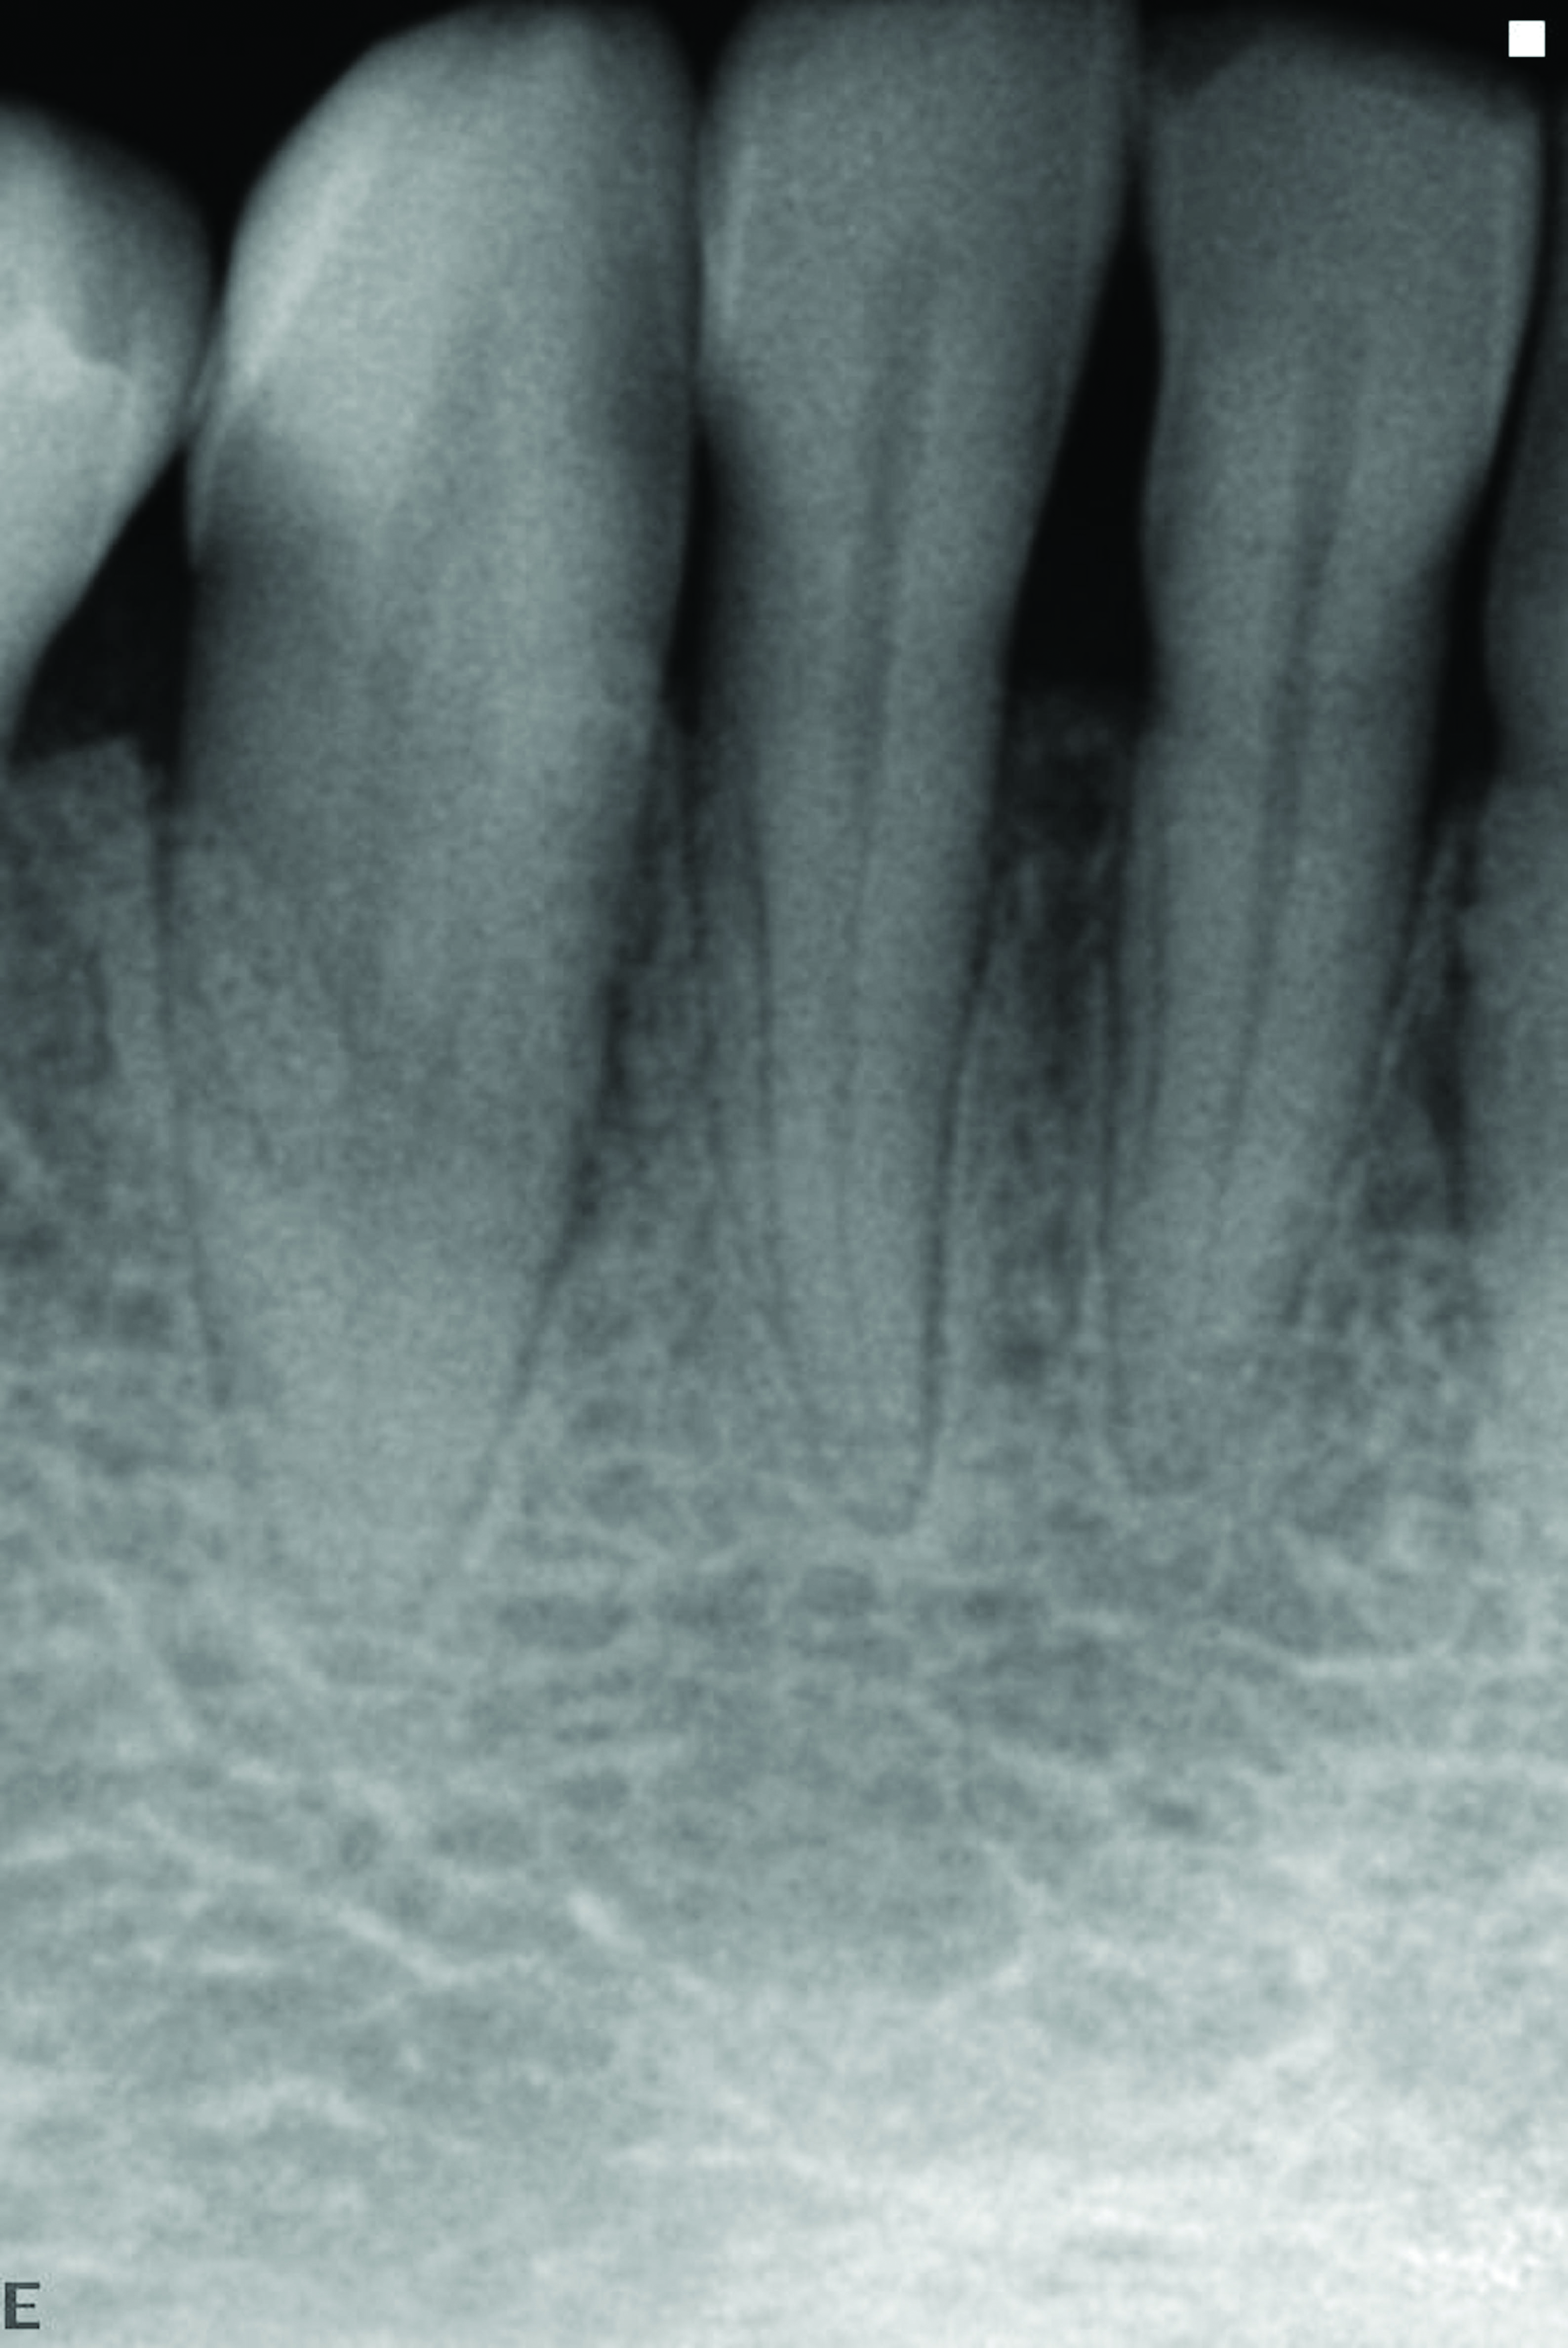

At the 13-month postoperative visit, the patient who had initially been referred for extraction and an implant still has the tooth with minimal probing depths and no mobility (Figure 20). She reported that she is happy that she did not have to have her canine extracted.

The 13-month postoperative radiograph. Significant regeneration is suggested.

Figure 20